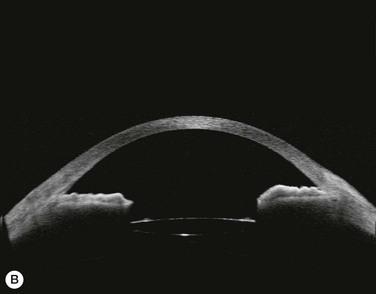

Substantial increases in anterior chamber depth and angle width following cataract extraction with intraocular lens (IOL) implantation have been demonstrated in eyes with PAC (Fig. 108-2A,B).23–25 The narrower the preoperative anterior chamber angle, the greater the alteration of angle configuration. Whereas iridolenticular contact was observed in a phakic eye, there was no iris and IOL contact in a pseudophakic one (Fig. 108-2A,B). The iris plane shifted backward, deepening the central anterior chamber by approximately 850 µm. Preoperative biometry performed in a series of 52 eyes of 48 consecutive Thai middle-aged patients who had developed acute PAC within 6 months showed that average natural lens thickness and central anterior chamber depth were 4.83 mm and 1.8 mm, respectively.26 Since the IOL (PMMA, silicone, acrylic) thickness in the 20–25 D power ranges from 0.75 mm to 1.42 mm. Replacement of the natural lens with the IOL provided up to 4 mm more axial distance within the anterior segment eliminating angle crowding and appositional closure. In addition, anterior chamber deepening with a viscoelastic during IOL implantation might break recent PAS.

Several studies have shown that extracapsular cataract extraction (ECCE) with IOL implantation is effective in opening the angle and controlling IOP in refractory PAC.27–30 Currently, ECCE has been replaced by phacoemulsification which offers a higher surgical success rate, less postoperative inflammation and fewer complications. In addition, the clear corneal approach spares the superior conjunctiva for possible filtering surgery, if needed. Phacoemulsification and IOL implantation has been reported to be highly effective in patients with uncontrolled PAC.31,32 However, up to 32% of the patients still had persistent PAS and required long-term treatment with glaucoma medication following lens removal either by ECCE or phacoemulsification and IOL implantation alone (Fig. 108-2A).5,32 Goniosynechialysis is the next step to eliminate the remaining synechiae and control the IOP (Fig. 108-2C).

Patients are treated with antiglaucoma medications and frequent topical steroids. When the inflammation subsides, the medications are then slowly tapered off within a month. Occasionally, a release of aqueous through the paracenteses at the slit lamp may be performed if a high IOP rise occurs. Gonioscopy typically reveals opening of the angle structures with irregular pigmentation on the newly exposed trabecular meshwork and the angle wall (Fig. 108-6). Angle recession or a cyclodialysis cleft are undesirable findings. If successful, anterior segment optical coherence tomography or ultrasound biomicroscopy should demonstrate separation of the PAS and reopening more than half of the entire angle (Figs 108-2, 108-7).